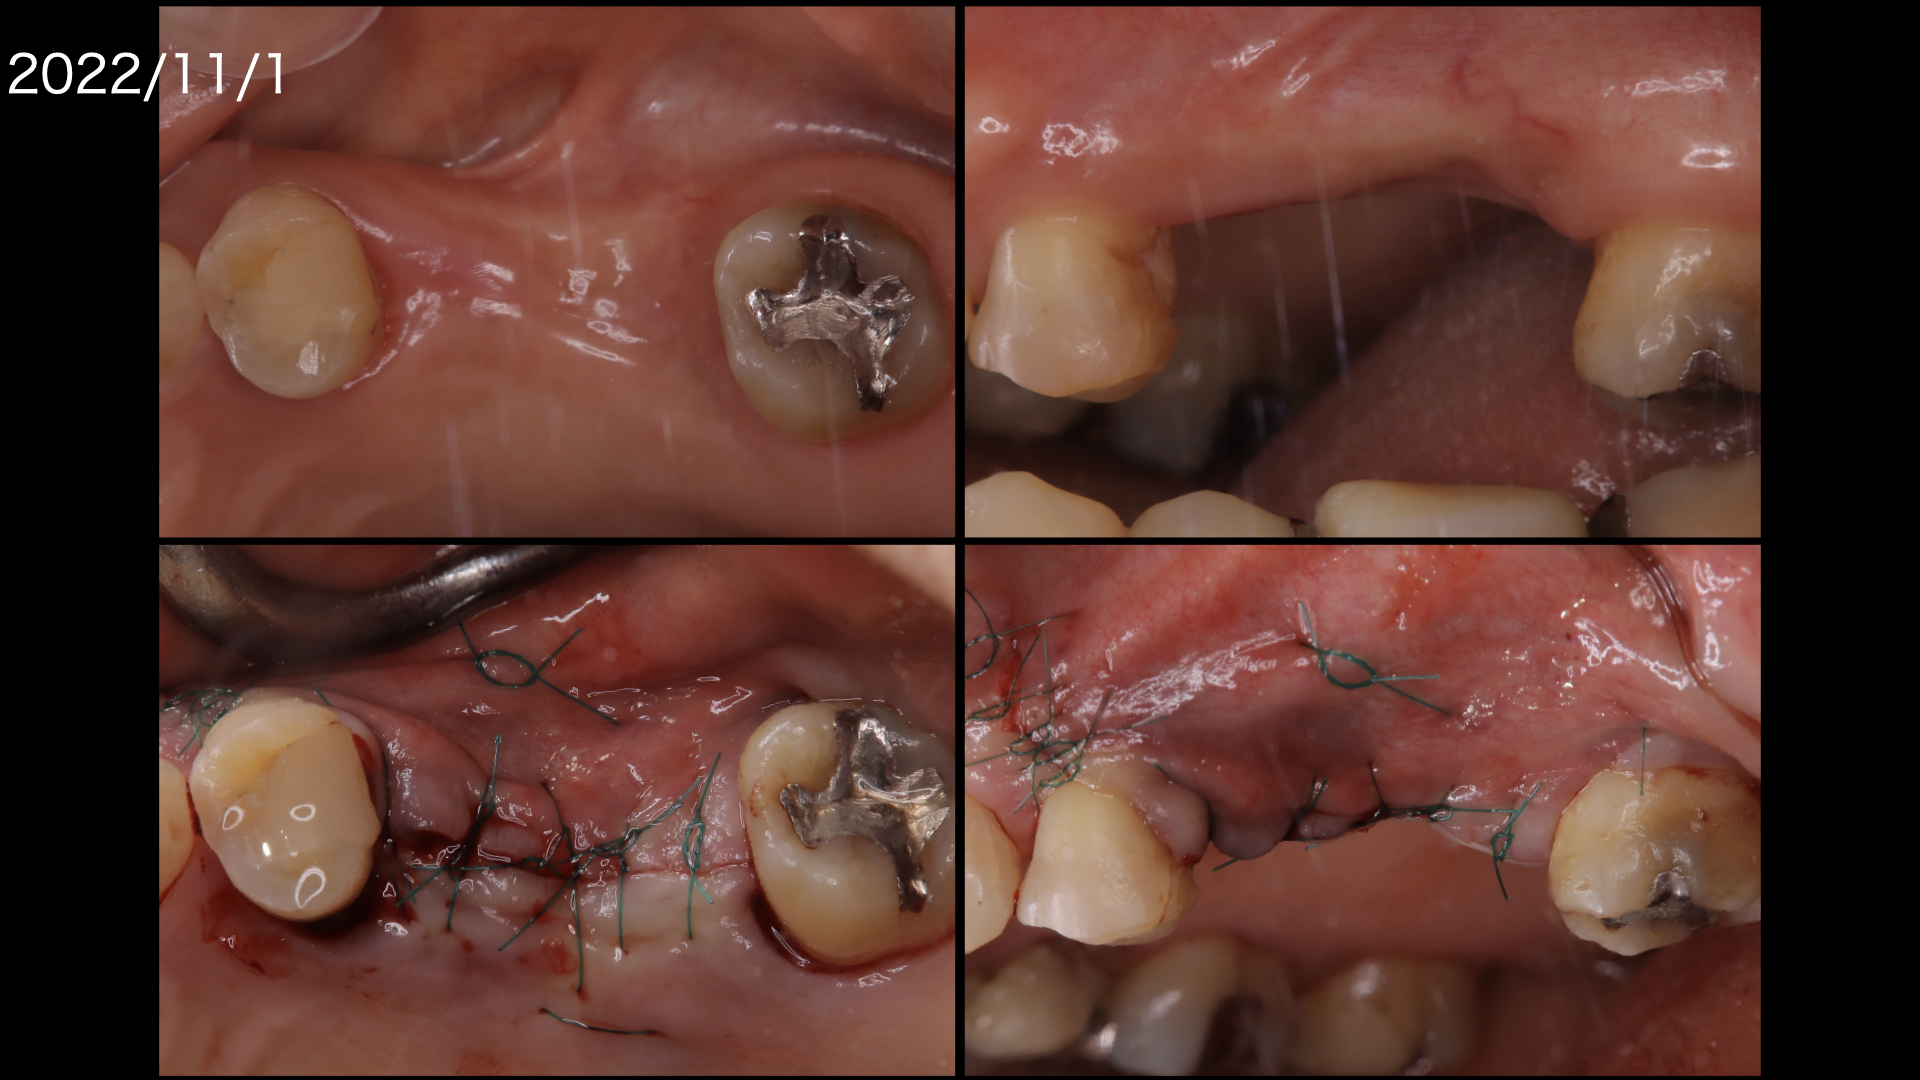

まずは奥から2番目の歯も保存を希望されましたが、治りが悪かったので一度抜歯して歯石を取り、戻してみて保存を試みました。

その間矯正治療をおこないました。

残念ながら、奥歯は腫れが引かず抜歯になってしまいました。

矯正が終わり、左上のインプラント治療に入ります。

もともと歯周病で骨が吸収していましたので、この部分にインプラントをおこなうには骨を造らなければなりません。

骨造成。またこの部分は上顎洞にも隣接しているので、上顎洞挙上術も必要です。

骨造成と上顎洞挙上術を同時に行いました。

骨造成したので、歯肉をかなり減張切開する必要がありました。

上の図:減張切開したため、頬側に角化歯肉が喪失しておりこのままでは歯ブラシがしにくい状態です。

下の図:口蓋側から歯肉を移植しました。(遊離歯肉移植:FGG).頬側の歯肉の形態がよくなりました。